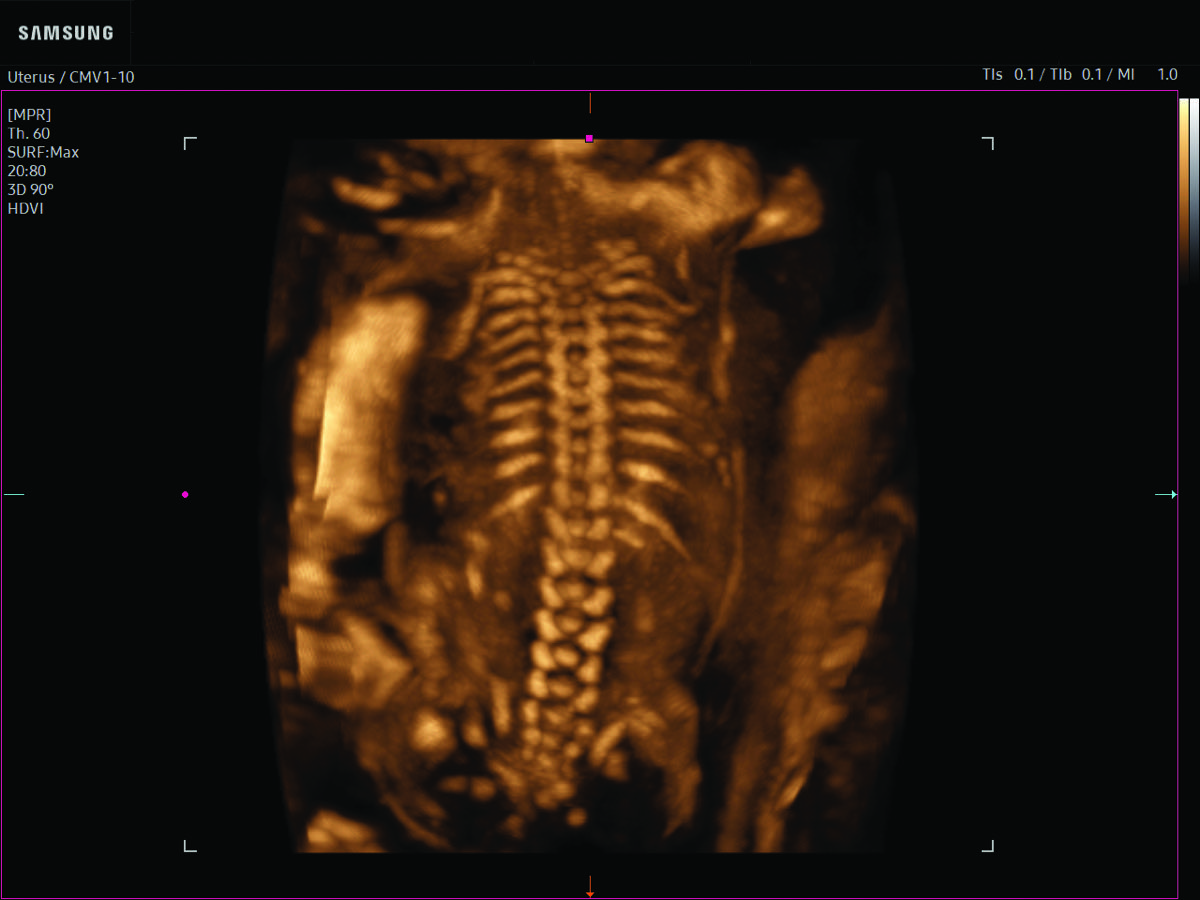

Procedural Services

Comprehensive, advanced and expert MFM care for high-risk pregnancies

- Fetal anomalies